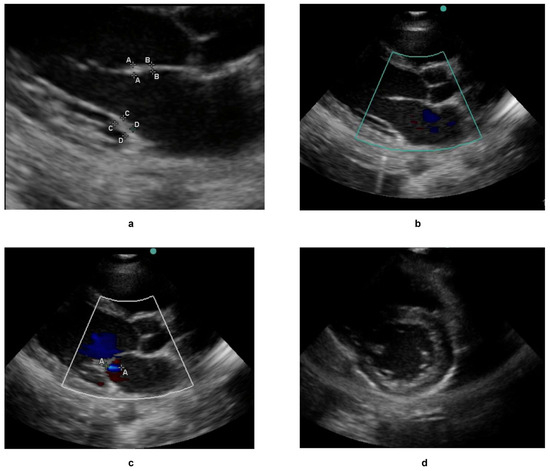

Self-Supervised Multi-Task Learning for the Detection and Classification of RHD-Induced Valvular Pathology

Lorna Mugambi, Ciira wa Maina, Liesl Zühlke